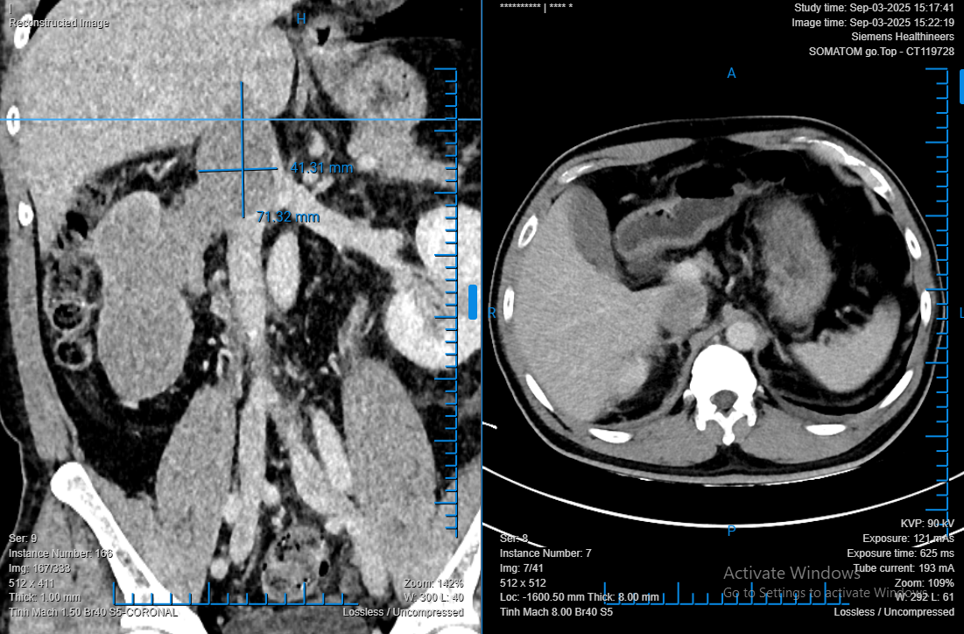

Theo khai thác bệnh sử, ông L. phát hiện bướu thận tình cờ trong lần khám sức khỏe định kỳ. Kết quả chẩn đoán hình ảnh cho thấy khối bướu chiếm gần toàn bộ thận phải, kích thước 68 x 86 x 138 mm, huyết khối lan sâu vào tĩnh mạch thận và tĩnh mạch chủ dưới.

TS.BS Phạm Phú Phát – Trưởng khoa Niệu A, Bệnh viện Bình Dân, cho biết bệnh nhân có nguy cơ tử vong nếu không được can thiệp kịp thời. “Ca mổ kéo dài liên tục 8 giờ, với sự phối hợp của bốn ê-kíp bác sĩ thuộc các chuyên khoa tiết niệu, gan mật, tim – mạch máu và gây mê hồi sức. Các bác sĩ lần lượt di động gan, bộc lộ tĩnh mạch chủ đoạn sau gan, cắt bỏ toàn bộ thận phải cùng huyết khối bướu trong tĩnh mạch. Khác với phương pháp truyền thống cần mổ mở để lấy huyết khối, ca mổ này được thực hiện hoàn toàn bằng phẫu thuật robot”, bác sĩ Phát nói.